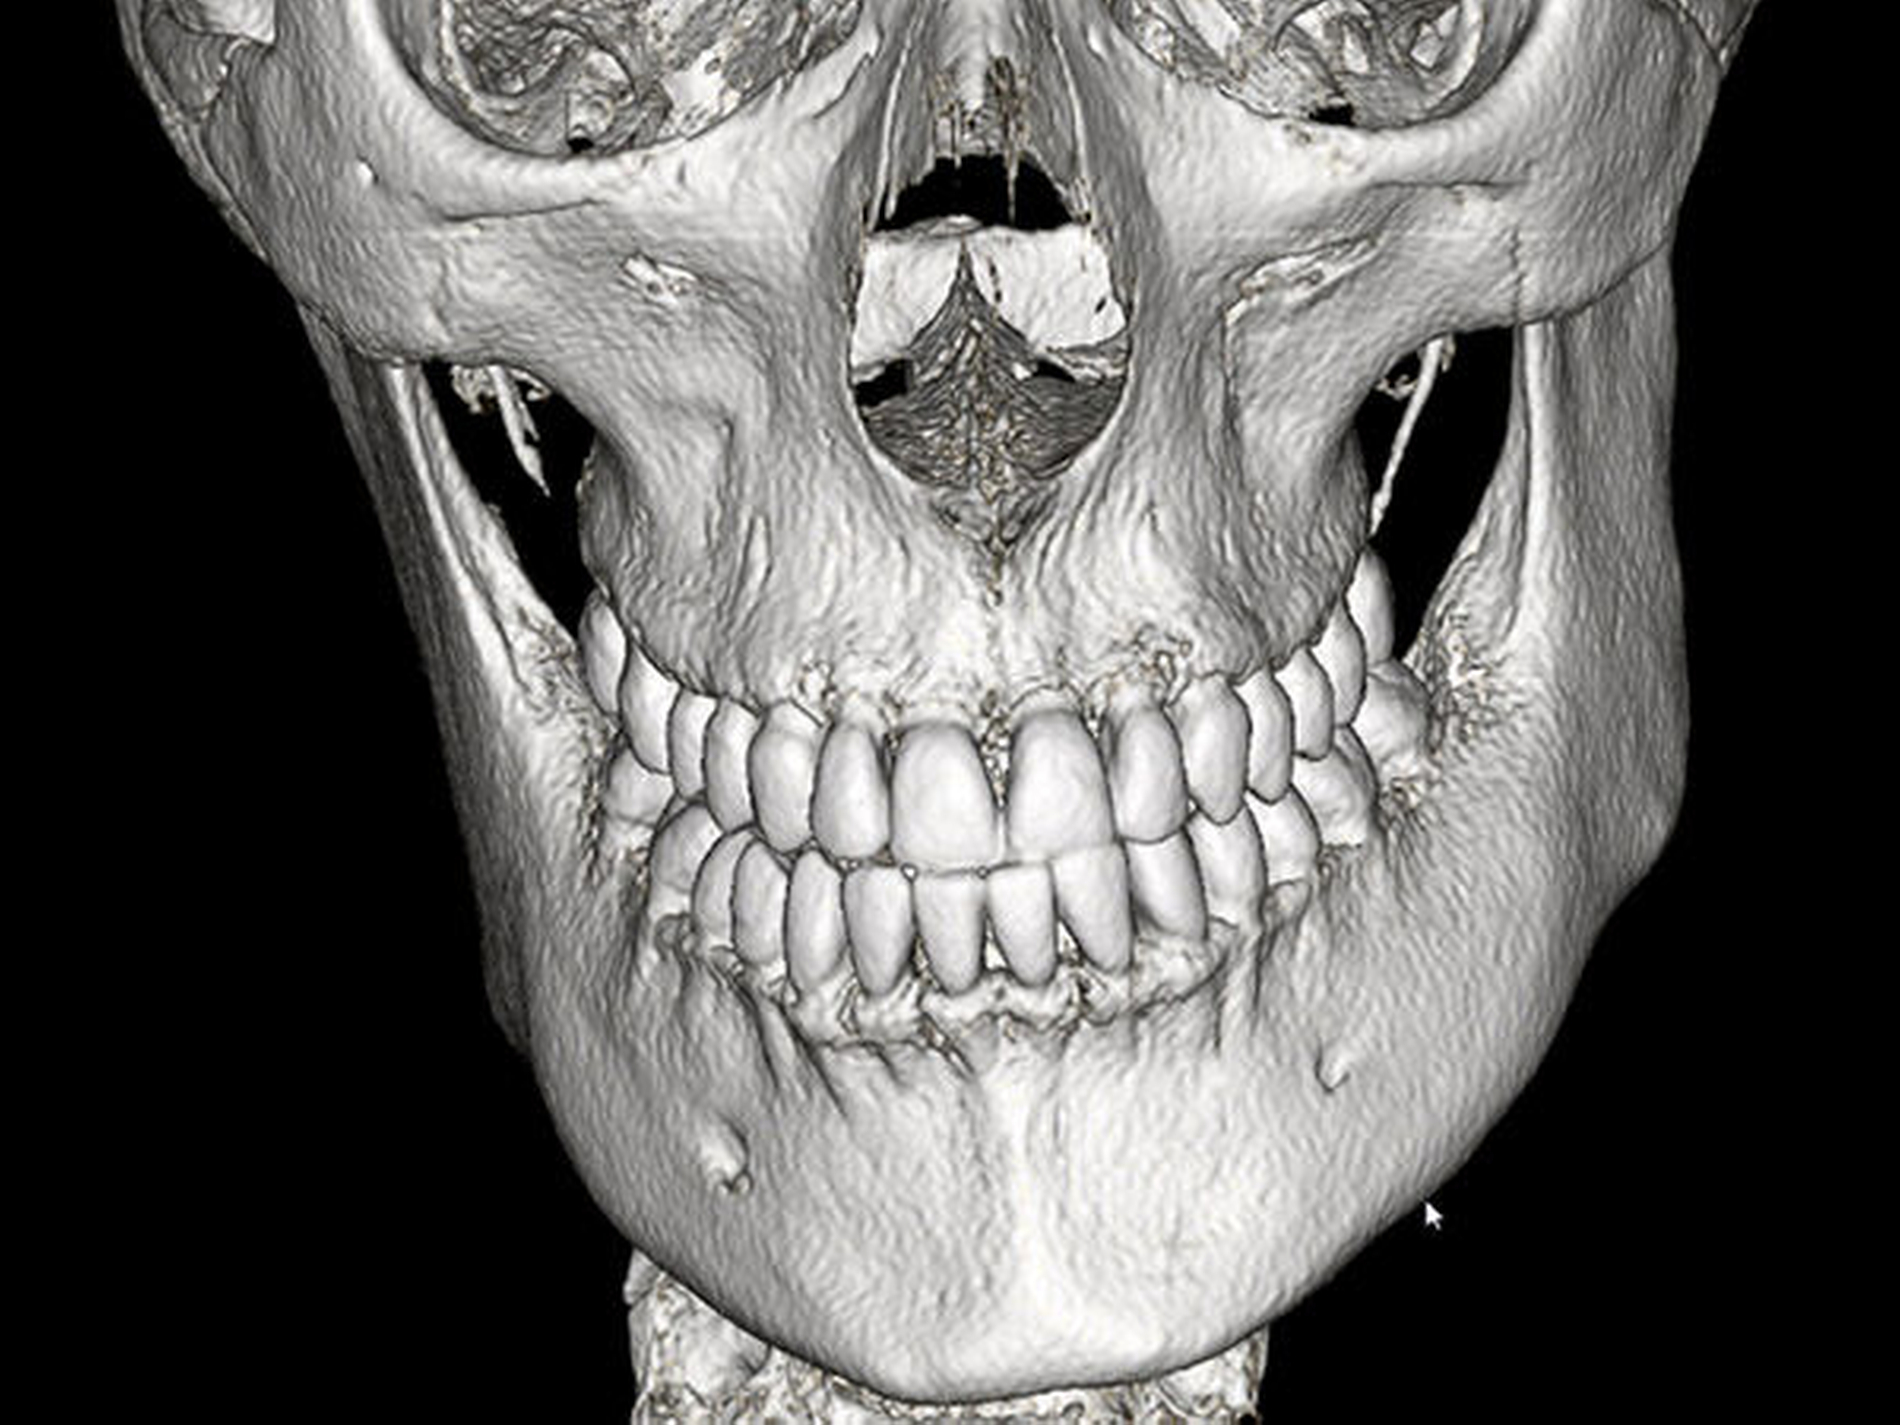

Mit Verdacht auf eine kondyläre Hyperplasie des rechten Unterkiefers wurde die Durchführung einer Skelettszintigrafie (Abbildung 3A) sowie einer CT-Bildgebung (Abbildung 3B) des Kiefers angeordnet. Hierbei konnte eine fokale Knochenstoffwechselanreicherung im Bereich des rechten Kiefergelenkköpfchens nachgewiesen werden. Die Kortikalis des rechten Kondylus war im Vergleich zur Gegenseite deutlich stärker ausgebildet, Hinweise auf eine tumoröse Raumforderung fanden sich in der CT nicht.